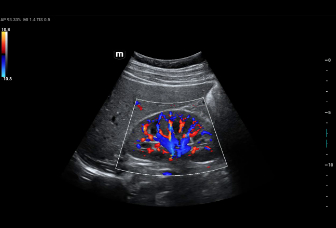

–ù–Ψ–≤–Β–Ι―à–Η–Ι –Ω–Ψ–¥―Ö–Ψ–¥ –Κ –Η–Ζ―É―΅–Β–Ϋ–Η―é ―¹–Ψ―¹―É–¥–Η―¹―²–Ψ–Ι –≥–Β–Φ–Ψ–¥–Η–Ϋ–Α–Φ–Η–Κ–Η: V Flow

–‰―¹–Ω–Ψ–Μ―¨–Ζ―É―é―²―¹―è –Φ–Α―Ä–Κ–Η―Ä–Ψ–≤–Α–Ϋ–Ϋ―΄–Β ―Ü–≤–Β―²–Ψ–Φ –≤–Β–Κ―²–Ψ―Ä–Α –¥–Μ―è –Η–Ϋ–¥–Η–Κ–Α―Ü–Η–Η –Ζ–Ϋ–Α―΅–Β–Ϋ–Η―è ―¹–Κ–Ψ―Ä–Ψ―¹―²–Η –Η –Ϋ–Α–Ω―Ä–Α–≤–Μ–Β–Ϋ–Η―è –¥–≤–Η–Ε–Β–Ϋ–Η―è –Κ–Μ–Β―²–Ψ–Κ –Κ―Ä–Ψ–≤–Η. –ë–Μ–Α–≥–Ψ–¥–Α―Ä―è ―¹–≤–Β―Ä―Ö–≤―΄―¹–Ψ–Κ–Ψ–Ι ―΅–Α―¹―²–Ψ―²–Β –Κ–Α–¥―Ä–Ψ–≤ V Flow –Ψ–±–Β―¹–Ω–Β―΅–Η–≤–Α–Β―² ―΅―Ä–Β–Ζ–≤―΄―΅–Α–Ι–Ϋ–Ψ ―΅–Β―²–Κ―É―é, ―²–Ψ―΅–Ϋ―É―é –Η –Ϋ–Β–Ζ–Α–≤–Η―¹–Η–Φ―É―é –Ψ―² ―É–≥–Μ–Α –Κ–Ψ–Φ–Ω–Μ–Β–Κ―¹–Ϋ―É―é –Ψ―Ü–Β–Ϋ–Κ―É ―¹–Ψ―¹―É–¥–Η―¹―²–Ψ–Ι –≥–Β–Φ–Ψ–¥–Η–Ϋ–Α–Φ–Η–Κ–Η ―¹ –≤–Ψ–Ζ–Φ–Ψ–Ε–Ϋ–Ψ―¹―²―¨―é –≤―¹–Β―¹―²–Ψ―Ä–Ψ–Ϋ–Ϋ–Β–≥–Ψ –Α–Ϋ–Α–Μ–Η–Ζ–Α.

V Flow

–ù–Ψ–≤–Β–Ι―à–Η–Ι –Ω–Ψ–¥―Ö–Ψ–¥ –Κ –Η–Ζ―É―΅–Β–Ϋ–Η―é ―¹–Ψ―¹―É–¥–Η―¹―²–Ψ–Ι –≥–Β–Φ–Ψ–¥–Η–Ϋ–Α–Φ–Η–Κ–Η: V Flow

–‰―¹–Ω–Ψ–Μ―¨–Ζ―É―é―²―¹―è –Φ–Α―Ä–Κ–Η―Ä–Ψ–≤–Α–Ϋ–Ϋ―΄–Β ―Ü–≤–Β―²–Ψ–Φ –≤–Β–Κ―²–Ψ―Ä–Α –¥–Μ―è –Η–Ϋ–¥–Η–Κ–Α―Ü–Η–Η –Ζ–Ϋ–Α―΅–Β–Ϋ–Η―è ―¹–Κ–Ψ―Ä–Ψ―¹―²–Η –Η –Ϋ–Α–Ω―Ä–Α–≤–Μ–Β–Ϋ–Η―è –¥–≤–Η–Ε–Β–Ϋ–Η―è –Κ–Μ–Β―²–Ψ–Κ –Κ―Ä–Ψ–≤–Η. –ë–Μ–Α–≥–Ψ–¥–Α―Ä―è ―¹–≤–Β―Ä―Ö–≤―΄―¹–Ψ–Κ–Ψ–Ι ―΅–Α―¹―²–Ψ―²–Β –Κ–Α–¥―Ä–Ψ–≤ V Flow –Ψ–±–Β―¹–Ω–Β―΅–Η–≤–Α–Β―² ―΅―Ä–Β–Ζ–≤―΄―΅–Α–Ι–Ϋ–Ψ ―΅–Β―²–Κ―É―é, ―²–Ψ―΅–Ϋ―É―é –Η –Ϋ–Β–Ζ–Α–≤–Η―¹–Η–Φ―É―é –Ψ―² ―É–≥–Μ–Α –Κ–Ψ–Φ–Ω–Μ–Β–Κ―¹–Ϋ―É―é –Ψ―Ü–Β–Ϋ–Κ―É ―¹–Ψ―¹―É–¥–Η―¹―²–Ψ–Ι –≥–Β–Φ–Ψ–¥–Η–Ϋ–Α–Φ–Η–Κ–Η ―¹ –≤–Ψ–Ζ–Φ–Ψ–Ε–Ϋ–Ψ―¹―²―¨―é –≤―¹–Β―¹―²–Ψ―Ä–Ψ–Ϋ–Ϋ–Β–≥–Ψ –Α–Ϋ–Α–Μ–Η–Ζ–Α.

V Flow